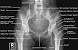

Pelvis Bone Anatomy Xray

Pelvis bone anatomy xray. The routine initial view of the pelvis is the anteriorposterior ap x ray figure 13 1 this image is obtained with the patient supine and the x ray beam oriented 90 degrees to the patients long axis passing through the patient from anterior to posterior. Ilium ischium and pubis. This bone if formed by the five sacral vertebral that are fused together to form a wedged shape bone that functions to supports the pelvis and transmits the weight of the body into the legs through the sacroiliac joints.

The 2 hemi pelvis bones and the sacrum form a bone ring bound posteriorly by the sacroiliac joints and anteriorly by the pubic symphysis. Hover onoff image to showhide findings. Ct mri radiographs anatomic diagrams and nuclear images.

An x ray of the pelvis focuses specifically on the area between your hips that holds many of your reproductive and digestive organs. Click image to align with top of page. Pelvis anatomy normal ap.